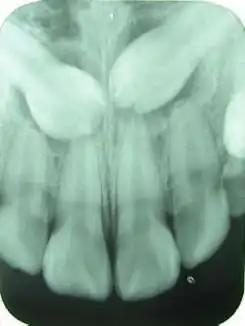

Der Mensch hat je einen Eckzahn pro Kieferhälfte im Unter- und Oberkiefer (insgesamt also vier). Der Eckzahn steht an dritter Position (es wird vom ersten Schneidezahn an gezählt) und ist der größte Zahn im Frontzahnbereich. Die Eckzähne bilden die Eckpfeiler am Übergang der Frontzähne zu den Seitenzähnen.

Meist brechen nach den Schneidezähnen im Oberkiefer erst die vorderen Prämolaren durch, bevor die Eckzähne durchbrechen. Im Unterkiefer ist es umgekehrt. Daher folgt der häufige Platzmangel für die oberen Eckzähne (siehe unten).

Neben den üblichen Zahnerkrankungen wie Karies, Pulpitis und apikaler Ostitis ist der obere Eckzahn sehr häufig retiniert und verlagert.

Ursache dafür ist die relativ späte Durchbruchszeit mit elf Jahren. In diesem Alter ist der Knochen bei manchen Kindern schon recht fest. Außerdem sind die bleibenden Nachbarzähne (zweiter Schneidezahn und erster Prämolar) schon vor dem Eckzahn da und können bei ausgeprägtem Platzmangel den gesamten Platz für den verspätet durchbrechenden Eckzahn einnehmen. Eventuell bricht der Eckzahn wegen Platzmangel auch weiter vestibulär durch – außerhalb der Zahnreihe. Er ragt dann wie ein Tigerzahn aus der vestibulären Wand des Alveolarfortsatzes.

Relativ häufig liegt der retinierte Eckzahn quer im Oberkieferknochen impaktiert.

Eine weitere Ursache für die Retention ist, dass der Eckzahn während seiner Bildungphase relativ weit oben im Kieferknochen liegt und einen sehr weiten Weg bis zum Zahndurchbruch zurücklegen muss.

Nach den Weisheitszähnen sind die Eckzähne die am zweithäufigsten betroffenen Zähne, die retiniert und verlagert sind. Ein persistierender Milch-Eckzahn im Oberkiefer deutet auf einen retinierten Eckzahn hin. Eine Nichtanlage der Eckzähne ist jedoch nicht bekannt bzw. extrem selten. Im Gegensatz dazu ist bei den Weisheitzähnen eine Nichtanlage häufig (ca. 50 %) und bei den benachbarten zweiten Schneidezähnen des Oberkiefers gelegentlich (ca. 1 %, familiär gehäuft) anzutreffen.